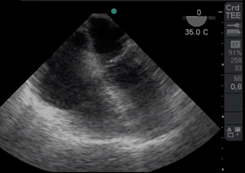

La salida de circulación extracorpórea (CEC) dificultosa es un evento que necesita ser reconocido para instaurar un tratamiento precoz. (Figura a)

Reconocer un ritmo de fibrilación ventricular y actuar desfibrilando de inmediato es el principal objetivo (Figura b), pero a continuación analizar la causa de la fibrilación, por ejemplo el ingreso de aire en la arteria coronaria derecha cuyo tratamiento es aumentar la presión de perfusión coronaria, reingresar a CEC y/o agregar s inotrópicos para aumentar la contractilidad; o una isquemia aguda de dicha arteria que lleva a la necesidad de realizar un puente venoso, tal es el caso de reconocer con ETE el signo de McConnel o signos de aumento de presión de cavidades derechas17. El aire puede ingresar también hacia la arteria pulmonar y observar esta situación a través de ETE nos obliga a informar al cirujano para lograr la completa desairación 18. (Figura cyFigura d)